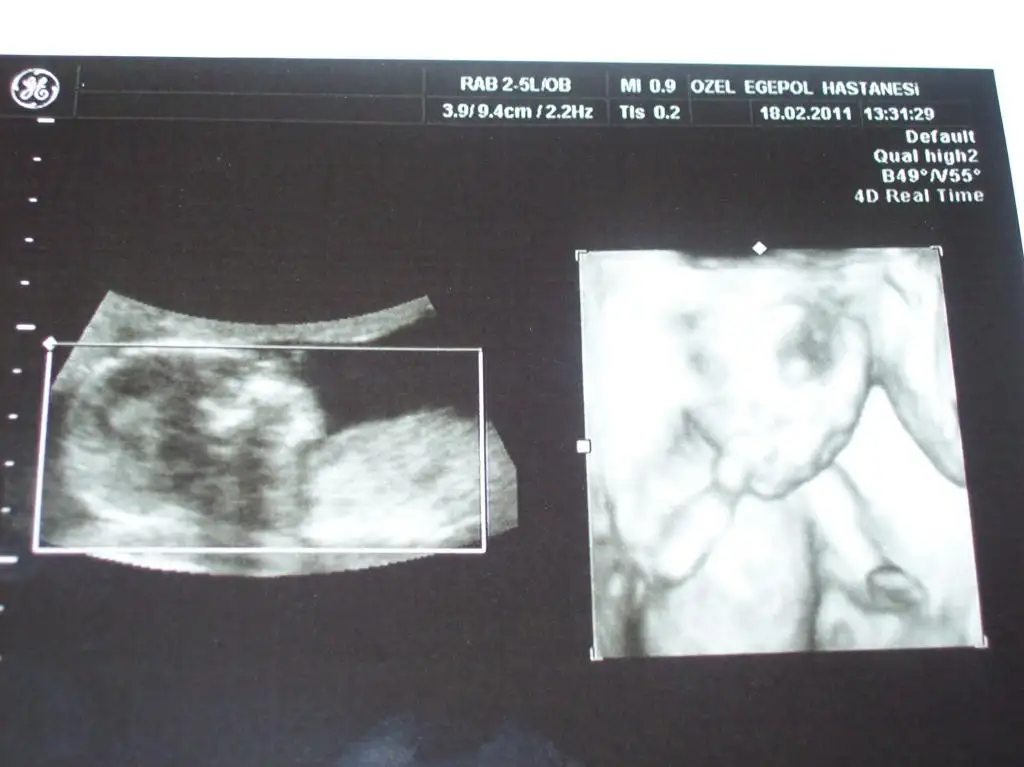

şimdi size göstercem ama aynı karede değiller ikisi ayrı çekti fotoları yüklüyom şimddiii:))

biri 10.80 cm diğeri11.76cm olmuş cnmmaasallah prenseslere kocaman olmuslar kıyamam yuzunu kapamıs